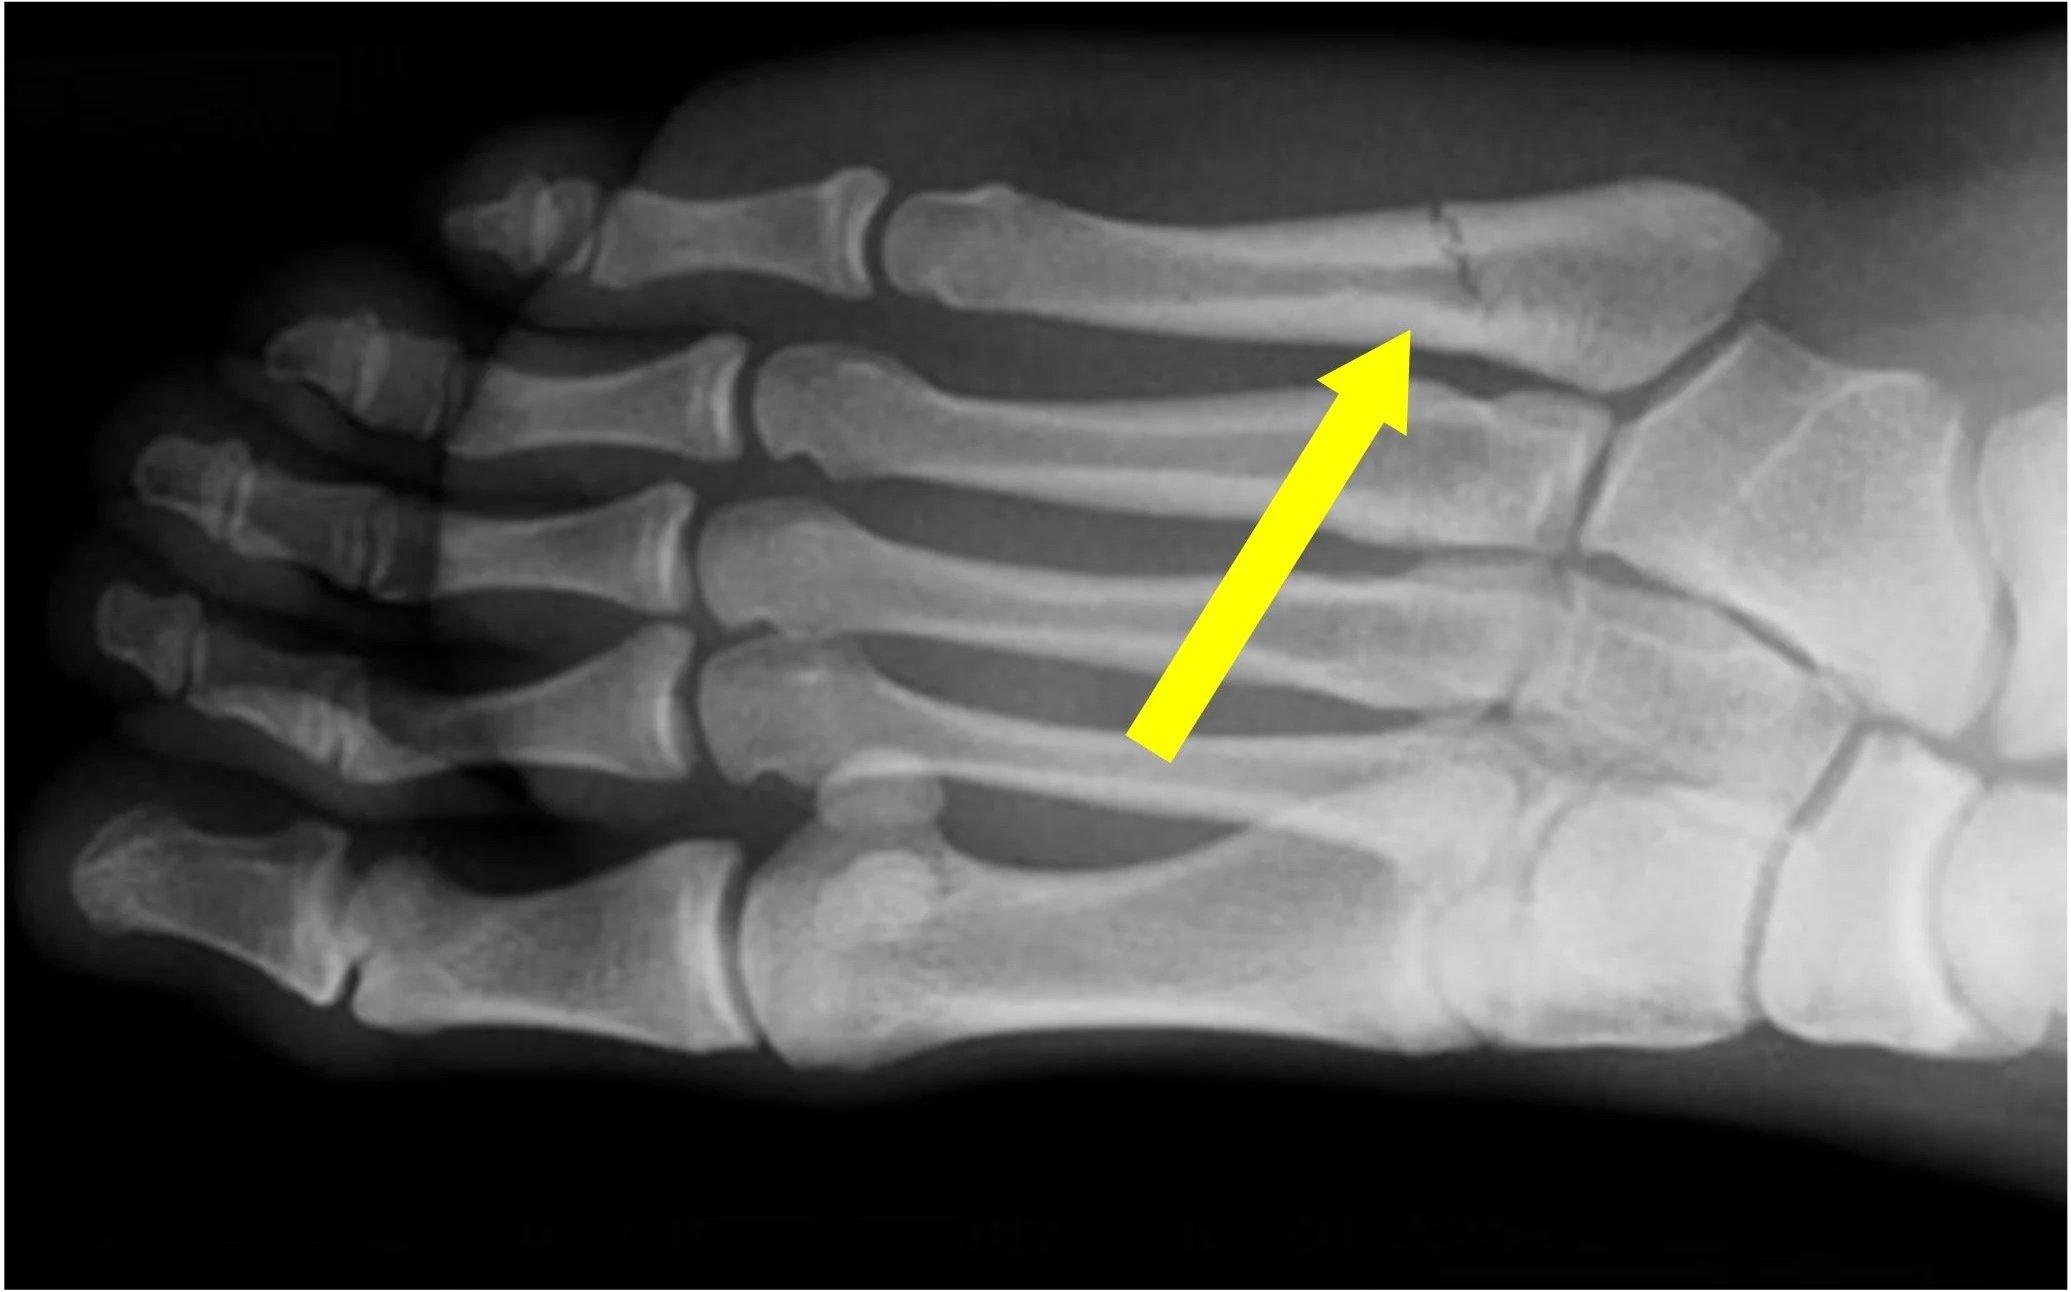

Midfoot Fractures

• Lisfranc Injuries: Critical injuries to the midfoot ligaments and bones.

• Navicular & Cuboid: Often related to stress or direct impact.

Forefoot Fractures

• Jones Fractures: A specific, high-risk break at the base of the 5th metatarsal.

• Metatarsal Stress Fractures: Common in runners and athletes.

• Toe (Phalangeal) Fractures: Breaks in the smaller bones of the toes.